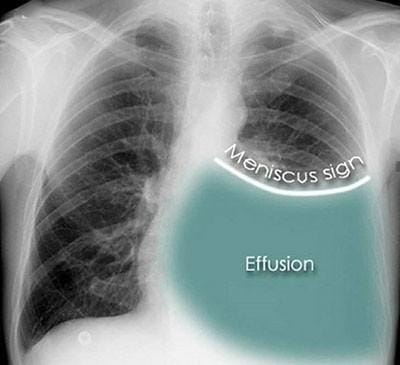

Chest X-ray: A meniscus sign on an upright posteroanterior chest X-ray is indicative of pleural fluid exceeding 200ml. Blunting of the costophrenic angle is also seen on the X-ray.

The lateral decubitus view can detect as little as 50 ml of fluid in the pleural space.